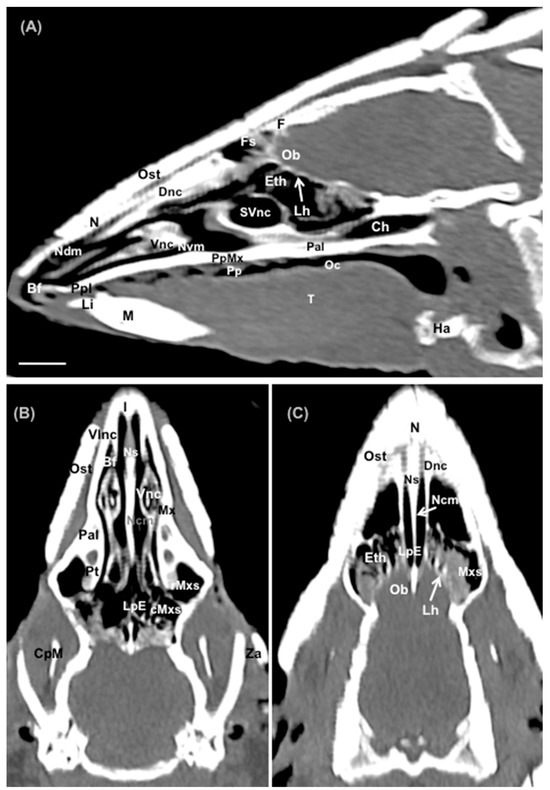

Abstract

3. Results

3.1. Anatomical Sections

3.2. Computed Tomography (CT)